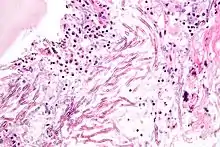

Infecting C. neoformans cells are usually phagocytosed by alveolar macrophages in the lung.[11] The invading C. neoformans cells may be killed by the release of oxidative and nitrosative molecules by these macrophages.[12] However some C. neoformans cells may survive within the macrophages.[11] The ability of the pathogen to survive within the macrophages probably determines latency of the disease, dissemination and resistance to antifungal agents. In order to survive in the hostile intracellular environment of the macrophage, one of the responses of C. neoformans is to upregulate genes employed in responses to oxidative stress.[11]